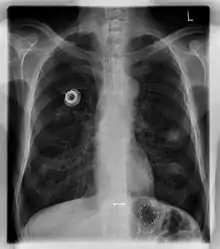

Chest X-ray showing an implanted port

The port is usually inserted in the upper chest (known as a "chest port"), just below the clavicle or collar bone, with the catheter inserted into the jugular vein.

A port consists of a reservoir compartment (the portal) that has a silicone bubble for needle insertion (the septum), with an attached plastic tube (the catheter). The device is surgically inserted under the skin in the upper chest or in the arm and appears as a bump under the skin. It requires no special maintenance other than occasional flushing to keep clear. It is completely internal so swimming and bathing are not a problem. The catheter runs from the portal and is surgically inserted into a vein (usually the jugular vein or less optimally the subclavian vein). Ideally, the catheter terminates in the superior vena cava or the right atrium. This position allows infused agents to be spread throughout the body quickly and efficiently.